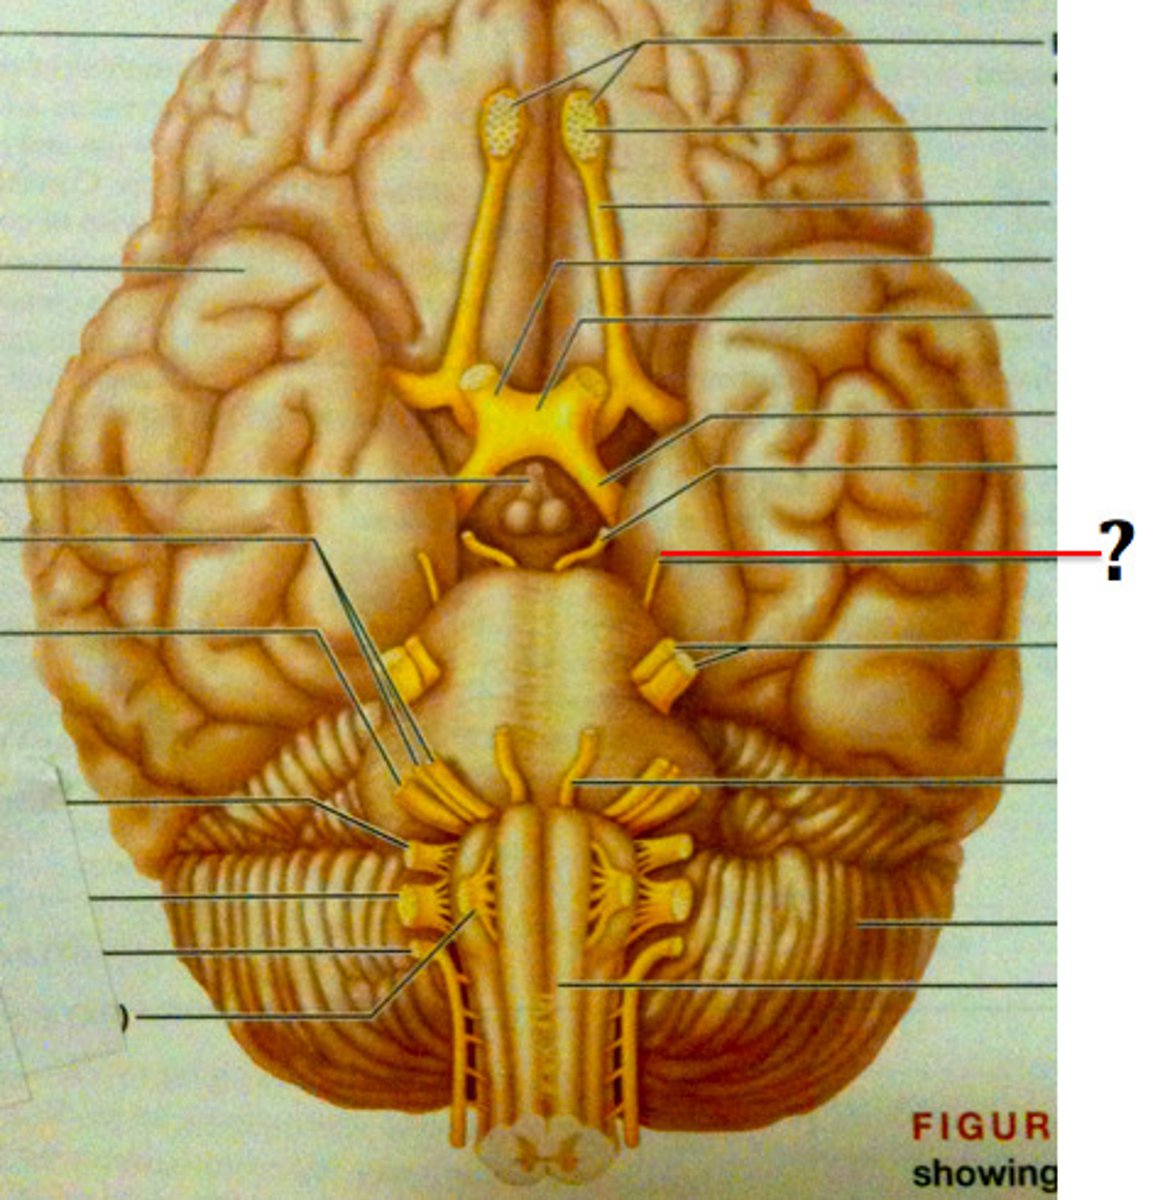

branches of olfactory nerve (cranial nerve I)

double check this

olfactory bulbs

olfactory tracts

double check this

optic nerves (cranial nerve II)

optic chiasma

optic tracts

CNIV (trochlear nerve)

CNVI (abducens nerve)

CNIII (oculomotor nerve)

CNVIII (vestibulocochlear) (acoustic nerve)

CNX (vagus nerve)